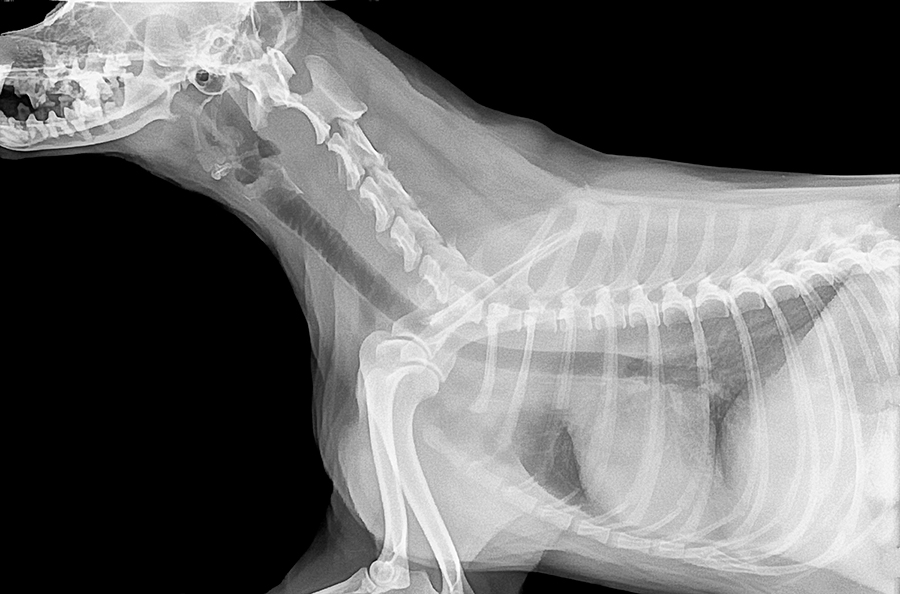

Las diversas patologías que pueden afectar a nuestro perro, pueden darse en múltiples tejidos. Y los huesos no están exentos de ellas, siendo los más afectados por la osteoporosis. Veamos en detalle cómo afecta la…